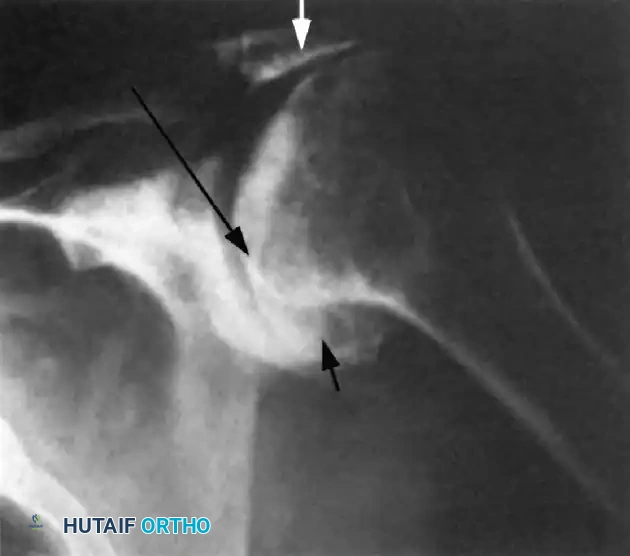

Radiographic Hallmarks

Standard radiographic evaluation must include a true anteroposterior (Grashey), scapular Y, and axillary lateral view. The classic radiographic findings of a chronic massive rotator cuff tear progressing to arthropathy include:

1. Superior Migration: An acromiohumeral interval (AHI) of less than 7 mm.

2. Loss of Joint Space: Progressive narrowing of the glenohumeral articulation.

3. Humeral Head Osteophytes: Inferior osteophyte formation due to altered loading.

4. The "Sourcil Sign": Sclerosis and erosion of the inferior acromial surface as the humeral head chronically "articulates" against the undersurface of the acromion.

Image